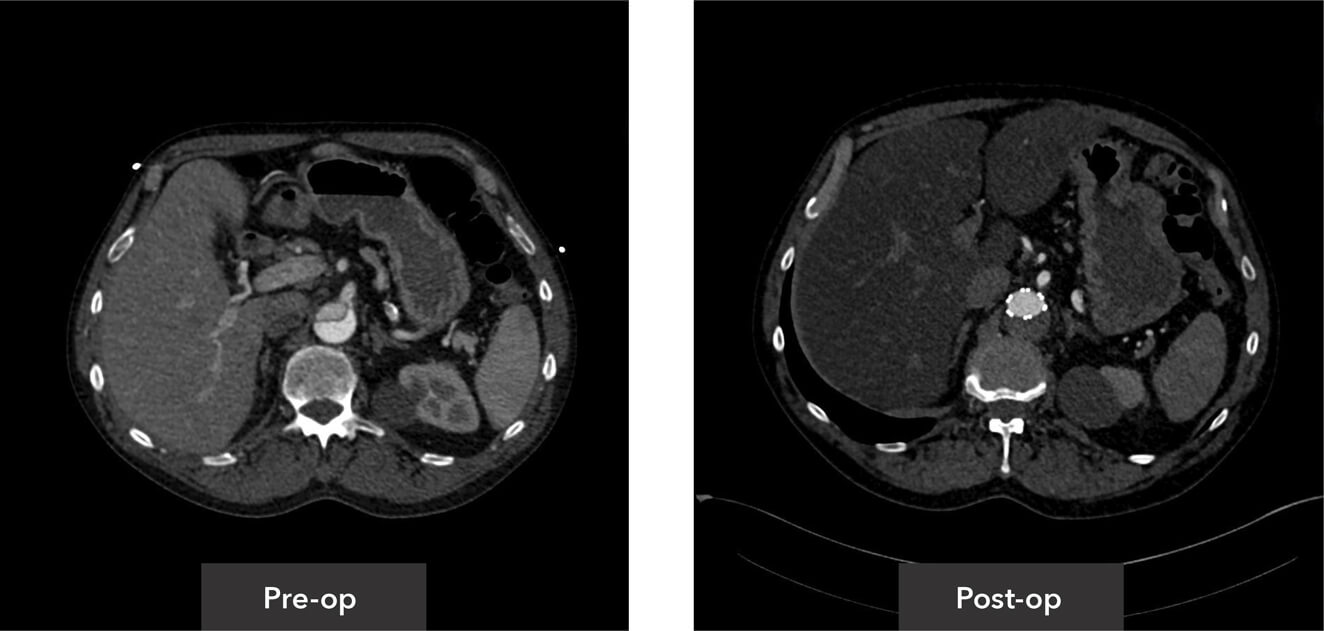

Visceral segment view pre-op/post-op axial view CT imaging

Abdominal aorta view pre-op/post-op axial view CT imaging